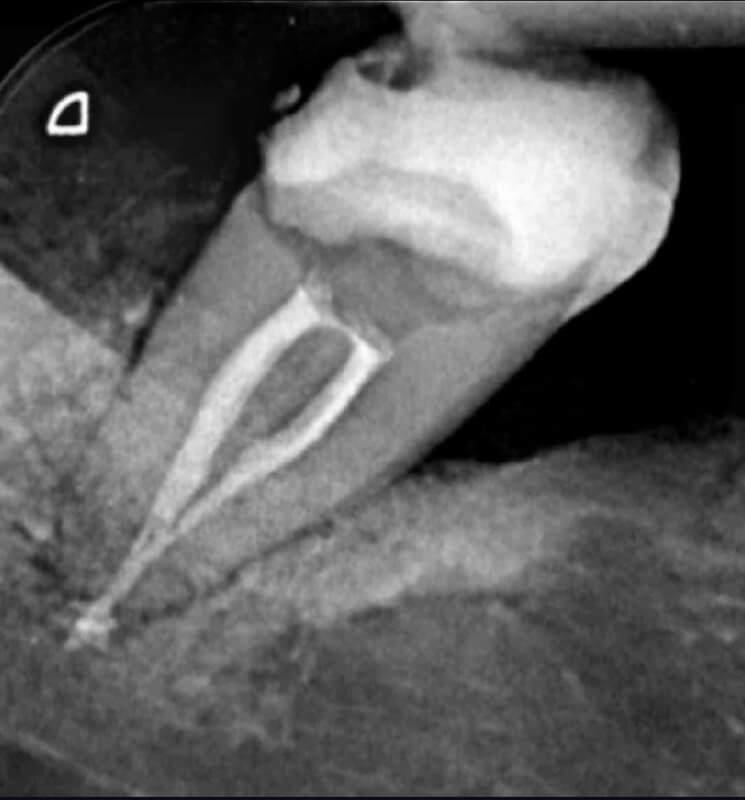

Tratamentele endodontice permit păstrarea dintelui natural, evitând extracția și menținând funcționalitatea acestuia.

Tratamentele corecte reduc riscul de infecții și complicații viitoare.